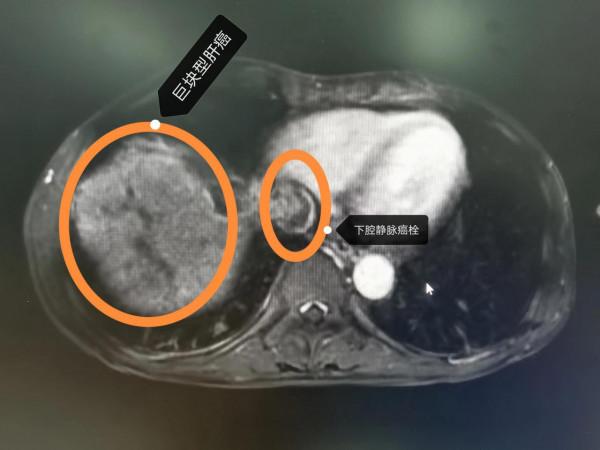

晚期肝癌的病人也不要輕易放棄!近2-3年,晚期肝癌的治療獲得了較大的突破,介入治療+靶向藥+PD1的治療組合,大部分情況下可以取得不錯的治療效果。這是一例非常晚期的肝癌病人,這要是在2-3年前,估計就是勸病人回家,該吃吃該喝喝,預計不會超過3個月的生存期。本例患者巨塊型肝癌合併下腔靜脈癌栓(下腔靜脈幾乎完全堵塞並臨近心房口了)及門靜脈主幹及右支癌栓的病人,經過2次的介入治療(肝動脈灌注化療術(HAIC)後,病灶明顯的縮小,癌栓明顯的消退,腫瘤指標直線下降,整個人的精神狀態持續好轉,未來可期。